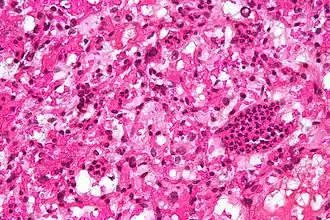

![]() Micrografía de un hemangioblastoma cerebeloso. Tinción HPS. | ||

Histológicamente, se trata de un tumor muy vascularizado. En el subtipo reticular, más frecuente, se puede ver entre la densa red capilar células grandes con citoplasma claro, a menudo vacuolado, denominadas células estromales y cuya histogénesis es aún poco conocida. Más raro es el subtipo celular, descrito por Harvey Williams Cushing y Percival Bailey, en el que las células estromales se disponen en un patrón alveolar, con un aspecto histológico que recuerda al del paraganglioma.[2][11]